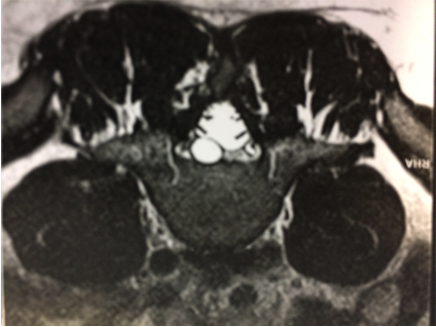

IRM lombaire

L’IRM lombaire met en évidence une hernie discale exclue, car il n’y a pas d’argument pour une lésion du mollet ou de la hanche et que l’infiltration semble avoir réglé le problème de la tendino-bursite du moyen fessier. En revanche, on est devant une lombalgie avec de discrets signes neurologiques et une douleur qui peut faire évoquer une sciatalgie.